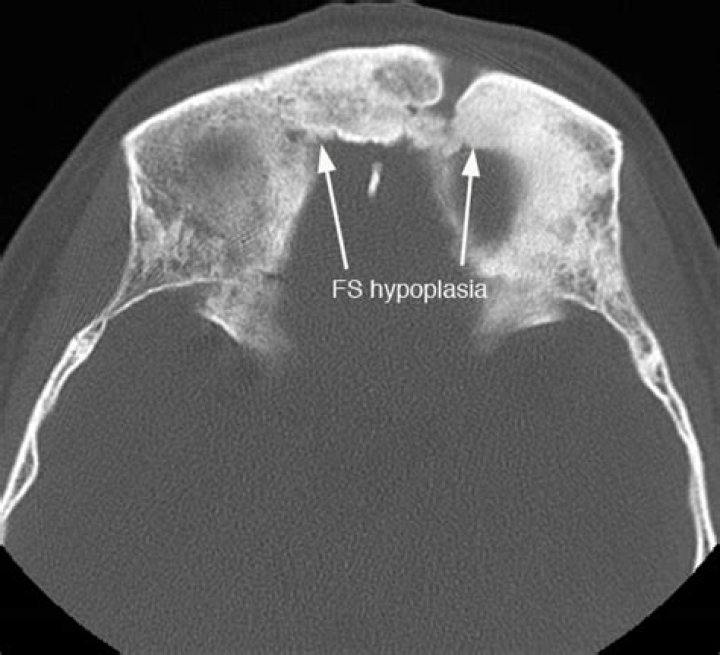

Hypoplasia or underdevelopment of the frontal sinuses is an unusual phenomenon. Computed tomography (CT) scans must be performed to map sinus anatomy and to assess the extent of the pathologic abnormality so that anatomical variants can be noted by the surgeon and complications can thus be avoided.

Decreased volume of frontal sinuses ; Small frontal sinuses ; Underdeveloped frontal sinuses. Narrow Synonyms: Decreased pneumatization of frontal sinus. Related Synonyms: Hypotrophic frontal sinus.